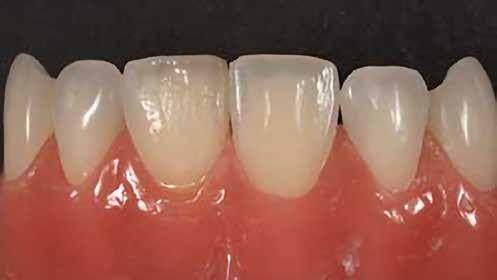

A fogászati kezelések során manapság már nem kizárólag az esztétikai megjelenés helyreállítására törekszünk. Sokszor a kedvezőtlen esztétikai megjelenés hátterében álló okok következményes módon a fogazat funkcionális működését is károsítják, így a kezelések során ezeknek a helyreállításával is foglalkoznunk kell. A különböző funkcionális és esztétikai diszkrepanciák kezelésére számtalan módszer létezik, ám ezen fogászati beavatkozások mindegyikében közös, hogy a kivitelezésük során nagyon szoros együttműködésre van szükség a kezelést végző fogorvos és a munkáját segítő fogtechnikus között. Az alábbi esetbemutatás során egy fiatal hölgypáciens fogazatának héjak alkalmazásával történő esztétikai és funkcionális rehabilitációját szeretnénk ismertetni.

A 19 éves hölgypáciens azzal a kéréssel jelentkezett a rendelőnkbe, hogy szebb fogakat szeretne. Az első konzultáció alkalmával megkérdeztük, hogy mi zavarja leginkább a fogazatának jelenlegi megjelenésében, valamint azt is megbeszéltük vele, hogy milyen végeredmény elérése esetén lenne maradéktalanul elégedett. Ebben az esetben a kezelési célokat az alábbiakban határoztuk meg:

A páciens fogazata esztétikai megjelenésének és funkcionális működésének a lehető legtöbb, saját foganyag megtartása mellett történő helyreállítása (1. és 3. ábra).